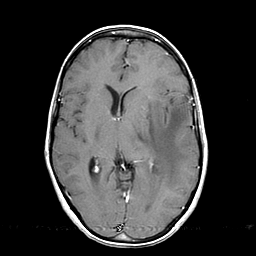

Metastatic bronchogenic carcinoma: T1-weighted MR -- Slice #11

[Home][Help][Clinical] Slice 11